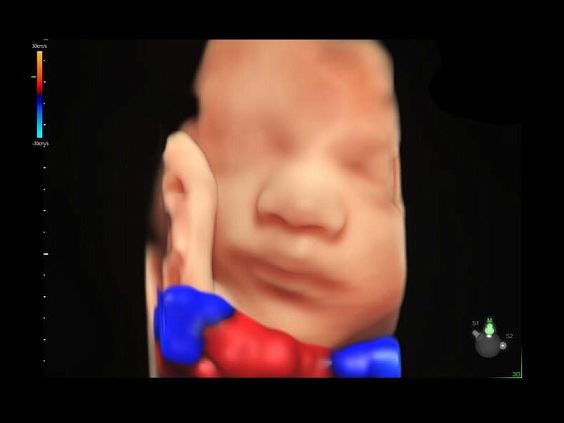

• Высокочувствительный допплер (HD-Flow)

• Реалистичный объёмный кровоток в режиме ЦДК (Radiantflow)

• HDlive Flow - перемещаемый источник света, совместимый с визуализацией кровотока в 3D

• HDlive Flow Silhouette - режим "Силуэт" с выделением границ полостей сердца и сосудов, совместимый с визуализацией кровотока

• Использование цветного, энергетического допплера, В Flow - режим STIC.

• Перемещаемый источник света - STICflow

• Технология HDlive Flow — повышает реалистичность визуализации сосудистых структур, улучшая восприятие глубины (по сравнению с традиционным цветовым допплером и функцией HD-Flow).